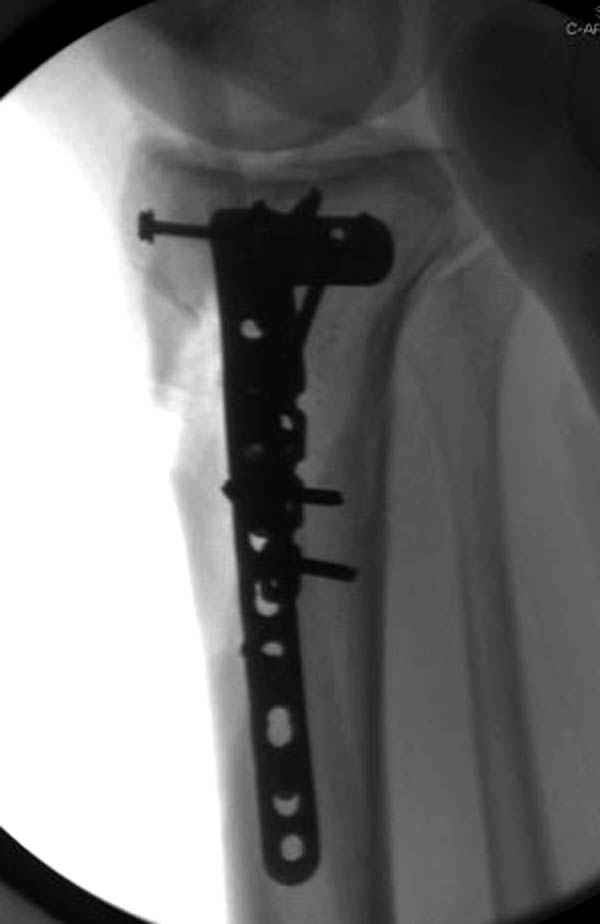

Трудно поверить, что разрекламированная Ортопедическая школа Восточной Украины позволяет такие странные снимки? На прямом снимке сохранен общий контур плато, но не известна судьба импрессии суставной поверхности. На полубоковой?, оставлен без репозиции задне-медиальный отдел, и навряд ли после такой фиксации можно удовлетвориться результатом.

Такая ситуация характерна для многих, когда принимается ошибочное решение, т.е пытаются фиксировать одним имплантом переломы двух мыщелков. Латеральная пластина приемлема только для тех случаев, когда сохраняется интактным медиальный диафизарный кортекс и отсутствует фрагментация на верхушке медиального перелома.

Здесь как раз тот случай, когда результат зависит не только от мастерства хирурга, но и от наличия современных методов исследования. Например, КТ которая поможет рассчитать направления шурупов и установку импланта. Кроме этого, поможет определиться с доступом.

Представленные снимки не информативны, нужны отдельные качественные снимки коленного сустава и голени без ротации.